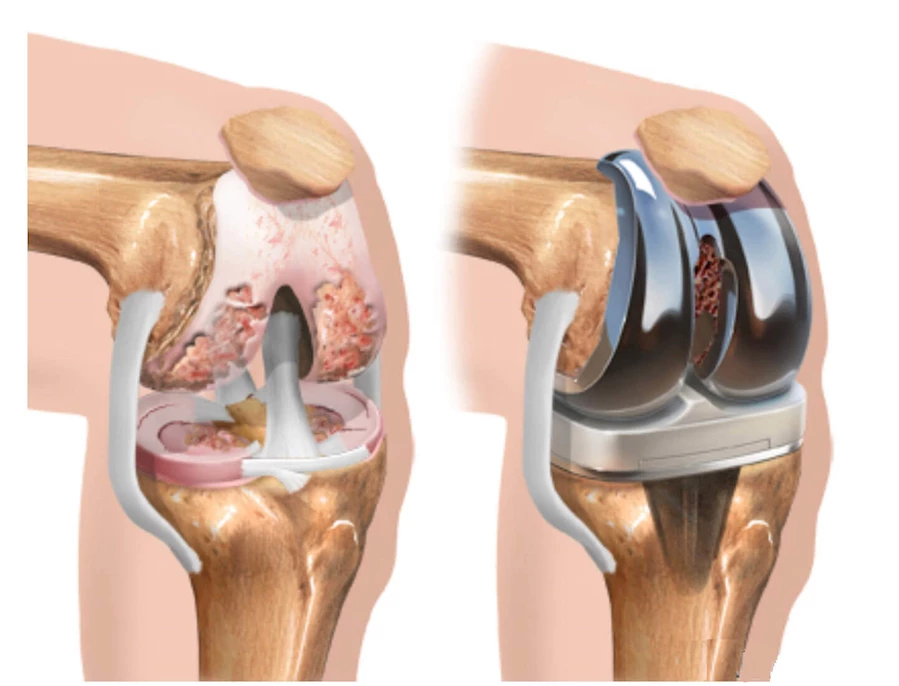

Diz protezi, diz eklemindeki hasarlı kıkırdak ve kemik dokusunun çıkarılarak yerine metal ve plastik bileşenlerden oluşan yapay bir eklem yerleştirilmesi işlemidir. En sık nedenleri arasında kireçlenme (osteoartrit), romatizmal hastalıklar, obezite, genetik yatkınlık, travmalar ve ağır spor aktiviteleri yer alır. Kadınlarda, özellikle 55 yaş üstünde, diz sorunları erkeklere göre daha yaygındır. Hemofili gibi kan hastalıkları veya çömelerek çalışma gibi alışkanlıklar da dizde yıpranmayı artırabilir.

En sık uygulanan yöntemdir; diz ekleminin tamamı metal ve plastik bileşenlerle değiştirilir.

İleri kireçlenme durumlarında tercih edilir.